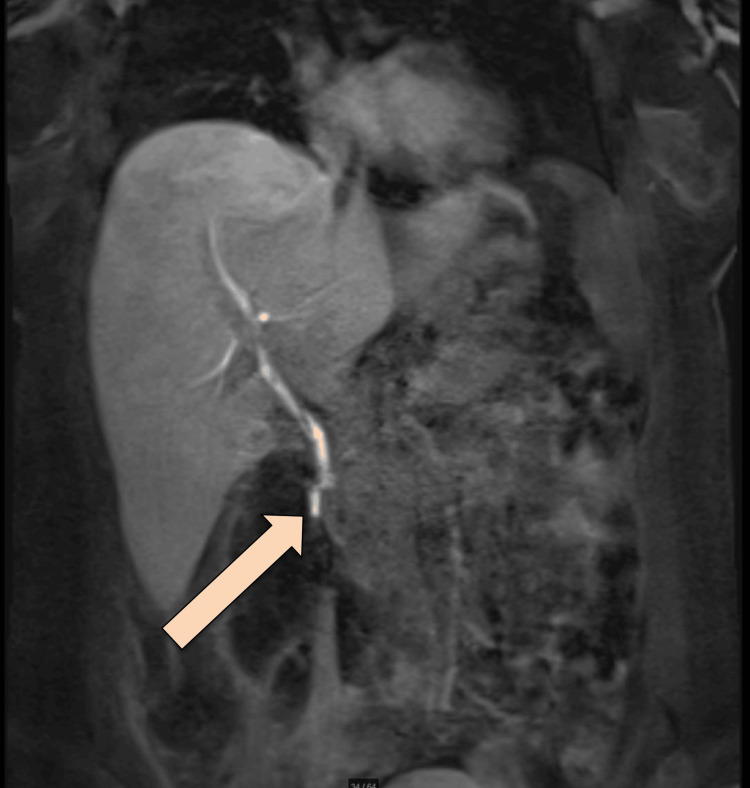

After the lungs were fully expanded in the chest X-ray, the chest tube was removed. The plan was to proceed with an MRCP Promovist to assess for a persistent biliary leak. Pooling/extravasation of Primovist into the retroperitoneal collection was observed, with the injury site likely at distal CBD at the level of the ampulla of Vater. The stable size of the multiloculated air-containing retroperitoneal collection was noted, with features suggesting a superadded infectious process (Figure 5).

MRCP was repeated, which showed delayed phases of the hepatocellular agent demonstrating opacification of the biliary tree with contrast reaching the second part of the duodenum without evidence of contrast leakage. However, 12 hours of delayed images showed a faint high signal at the expected site of the collection, possibly representing a persistent biliary leak. No significant biliary duct dilatation was observed. Expected minimal pneumobilia was noted (Figure 8).